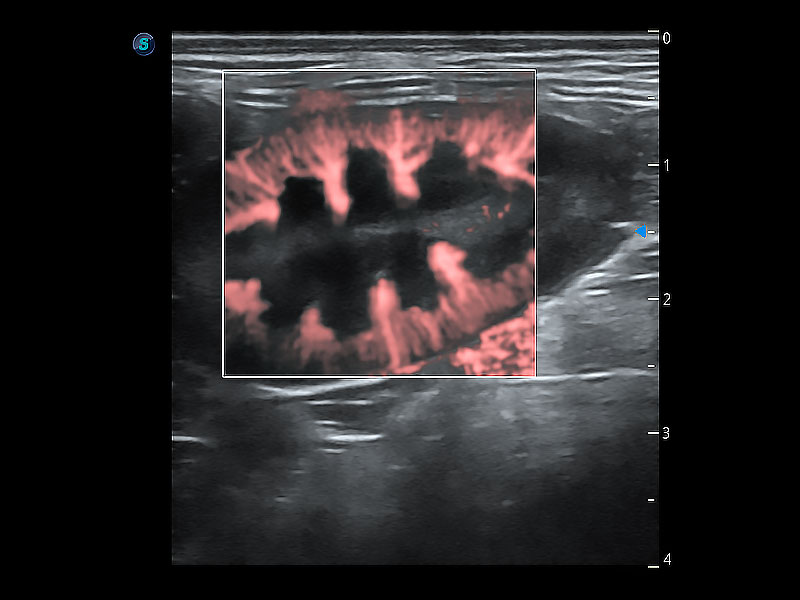

实时用颜色表示心肌组织运动,观察和定量组织的运动情況,对快速检测与评估心肌的灌注和活性、电传导及心肌收缩和舒张功能等均能提供重要的诊断信息。

通过心肌识别技术与二维斑点追踪技术相结合,对心脏的超声图像进行量化分析。计算心肌17个节段的应变、应变率、速度、位移等,并通过牛眼图的形式进行呈现。

通过360度任意调节3条M型取样线,在同一心动周期上观察心脏不同位置的运动曲线,得到准确的心功能测量数据,有效评估心肌运动及左心室功能。